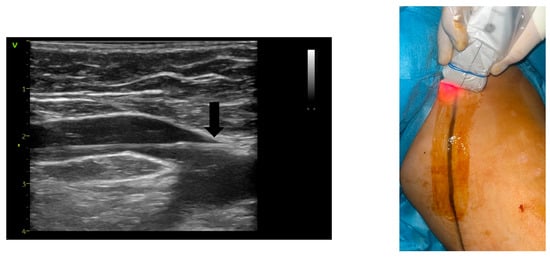

2. Materials and Methods